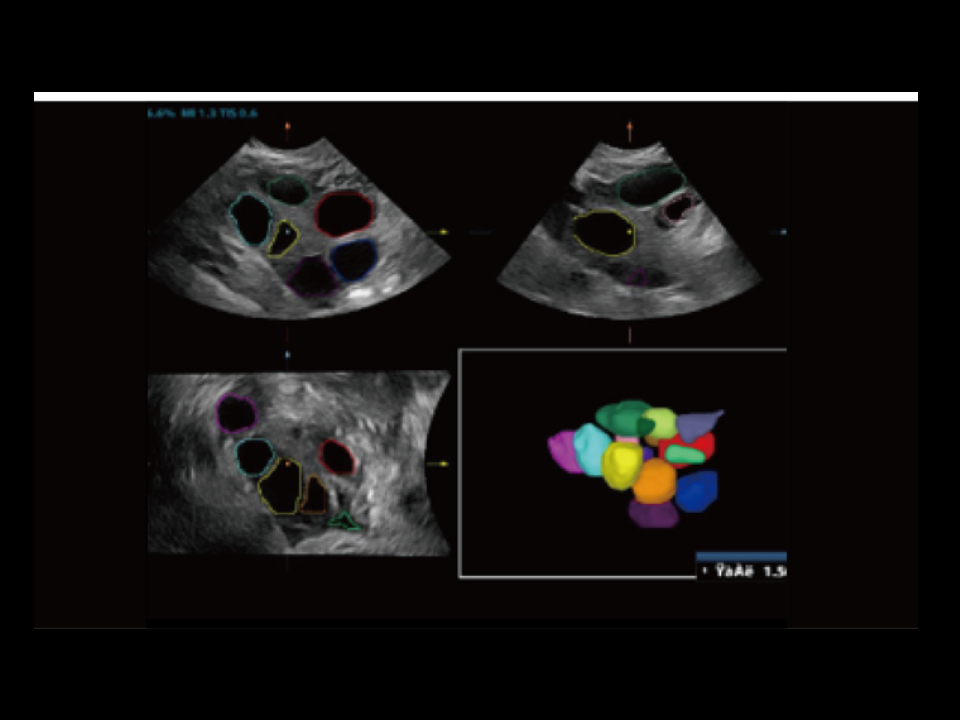

Since the company was founded, Mindray is continuously exploring new ways to improve diagnostic confidence. Powered by the most revolutionary ZONE Sonography? Technology, the ZST+ platform brings ultrasound image quality to a higher level by zone acquisition and channel data processing.

Thanks to the innovative, software-driven ZST+ platform, the Resona series is continuously evolving with the leading-edge technologies to meet the most challenging diagnostic demands in womenŌĆÖs health practice. More importantly, it is designed with the understanding that the wisdom of experts is always precious, and you need more intelligent partner for enhanced speed and confidence. Finally, Resona series with Zone Intelligence provides a total solution to help you with diagnostic confidence, efficiency, and standardization across different diagnostic challenges in todayŌĆÖs demanding and overburden hospital environment.